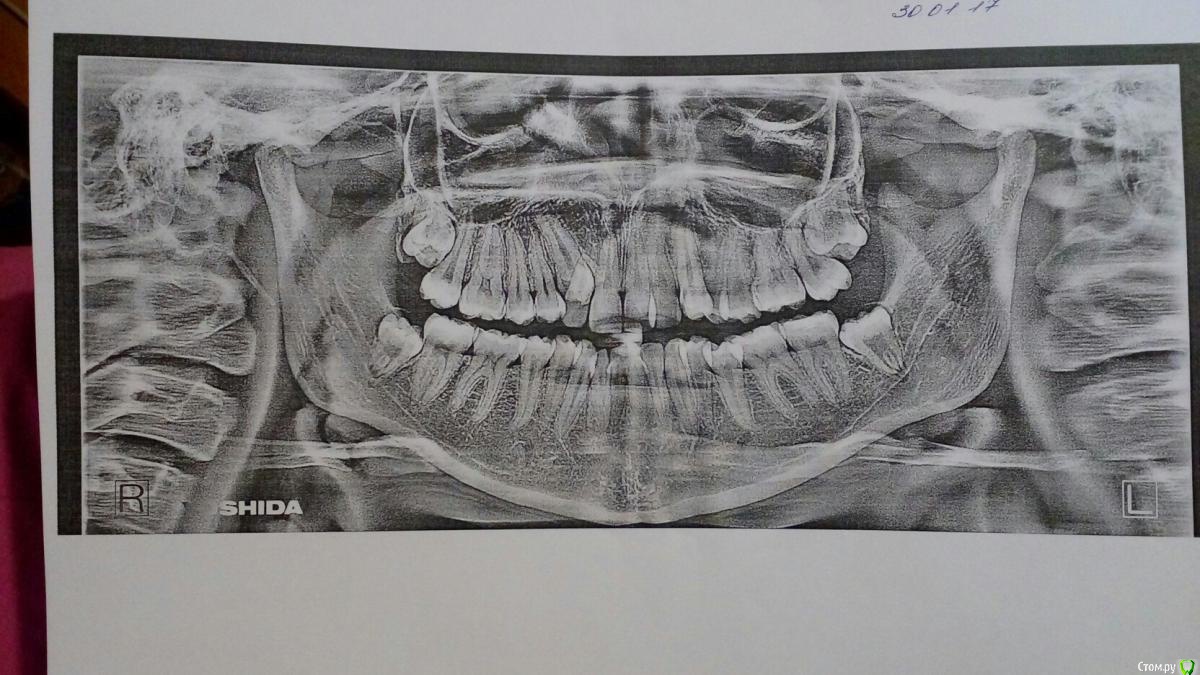

Здравствуйте, я хочу выровнять зубы. Мне 21 год. Пишу сюда потому, что не могу определится с линией лечения, так как у разных врачей разные варианты. Помогите мне пожалуйста.

Во первых у меня в верхней челюсти с правой стороны есть клык который не вырос в свое время, а начал прорезаться примерно пол года назад. За эти пол года он вырос на 1-1.5 миллиметра. (Прикрепляю фото сделанное с помощью зеркала, но клык практически не видно, обозначаю его место стрелочкой, и извините пожалуйста за качество фото)

Во вторых все врачи говорят, что перед установкой брекетов нужно удалять еще зубы. Разница в том какие именно.

1. Удалить 4 с левой стороны верхней челюсти. И 1 зуб с низу (какой не знаю).

2. Удалить 4 с левой стороны верхней челюсти и две 4 в нижней челюсти.

3. Удалить 4 с левой стороны верхней челюсти и две 5 в нижней.

4. Удалить 4 с левой стороны верхней челюсть в нижней ничего не удалять.

средние линии ни верхней ни нижней челюсти не совпадают со средней линией лица. это тоже должно стаять большим вопросом. это тоже нужно вложить в план лечения. как исправлять будете?